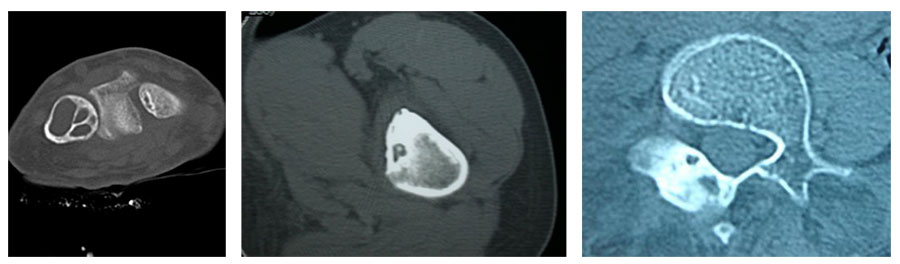

Опухоли костей являются редкими поражениями. Большая часть таких опухолей - доброкачественные образования, которые часто обнаруживаются случайно при радиологических исследованиях, проводимых по другим причинам. Что касается жалоб, они обычно проявляются отеком и болью. В редких случаях они обнаруживаются вследствие вызванного ими перелома в месте их расположения. Наиболее часто встречающимися доброкачественными образованиями являются остеоид-остеома, остеохондрома (экзостоз), энхондрома, неоссифицирующая фиброма, эозинофильная гранулема, простая костная киста, фиброзная дисплазия и внутрикостная липома / ганглия.